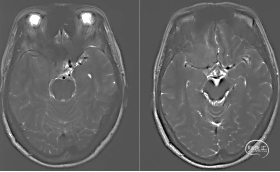

术后复查

术后MRI+增强

显示肿瘤完全切除。